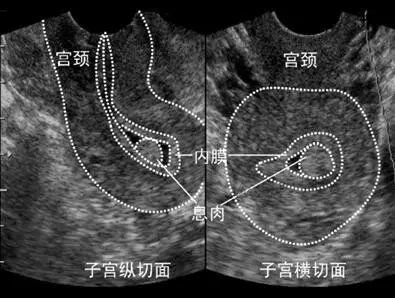

首先,进入试管婴儿(IVF)周期治疗前需行一次全面的超声检查。目的是初步测量子宫和卵巢的大小、筛查子宫畸形、附件或盆腔内病变和包块,评估双侧卵巢储备状况。必要时还需三维超声检查,进一步明确子宫及宫腔形态,以排除IVF治疗的禁忌症;

1)基础状态的超声监测:月经第1~5天进行,目的是评估盆腔的基础状态,包括卵巢、内膜评估和盆腔是否存在异常情况,为内膜准备方案提供依据。

3)激素替代周期:根据药物的使用时间进行超声监测,关注点主要是内膜的厚度及分型,直至确定您的移植日期。